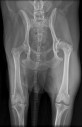

RadioQuiz 31 – Chien qui boite, la réponse

RadioQuiz 29 – Boiterie chronique

RadioQuiz 8

RadioQuiz 6 – la suite

RadioQuiz 6 – Ma p’tite chienne a mal à la patte

RadioQuiz 3: Docteur, mon chien boite…